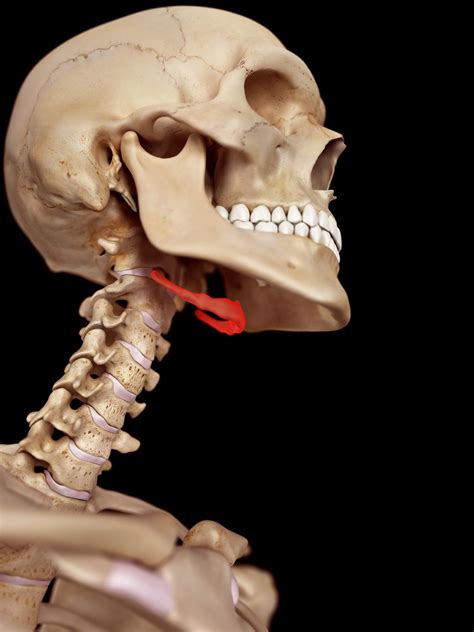

Understanding the intricacies of the human body can often lead to fascinating discoveries, especially when it comes to lesser-known conditions. One such condition is Hyoid Bone Syndrome, a term that might not be familiar to many but is crucial for those who experience it. This syndrome involves the hyoid bone, a small, U-shaped bone located in the neck between the chin and the thyroid cartilage. While it plays a vital role in supporting the tongue and various muscles, issues with the hyoid bone can lead to a range of symptoms and complications.

The hyoid bone is a unique structure in the human body. Unlike other bones, it does not articulate with any other bones; instead, it is suspended by muscles and ligaments. Its primary functions include: